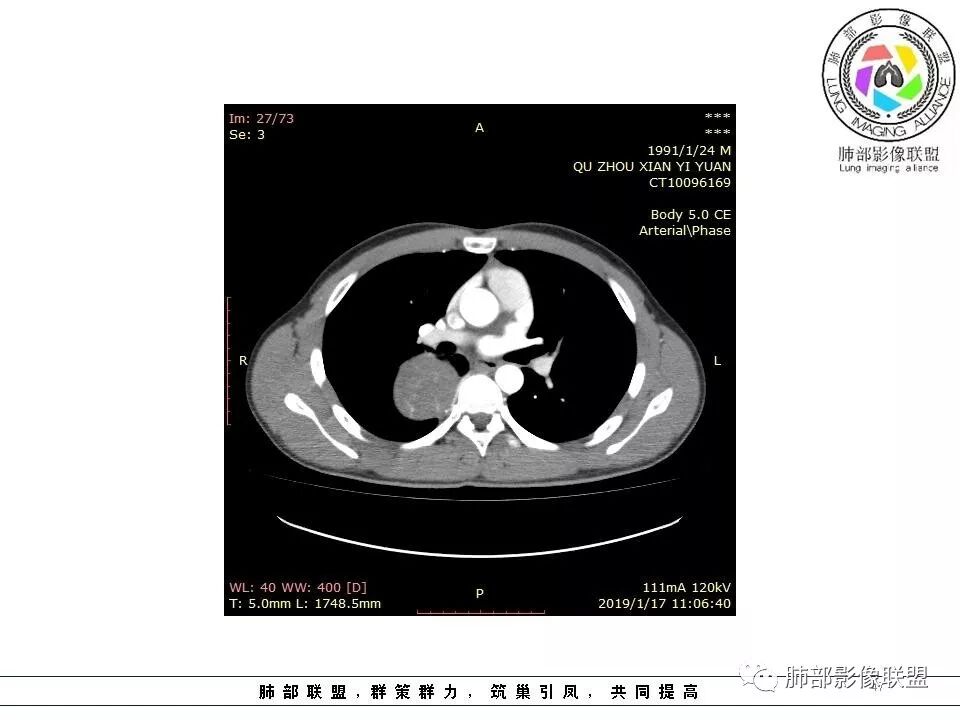

右后纵膈脊柱旁软组织占位,形态规则类圆,边缘光整,肺组织受压,胸膜尾,肋间动脉供血。中度不均匀延迟强化。

右后纵膈脊柱旁软组织占位,边界清晰,光整,肺组织受压。胸膜被掀起,肋间动脉供血,中度不均匀延迟强化。考虑神经鞘瘤,不除外纤维瘤

右后纵膈脊柱旁软组织影,与纵隔结构分界不清,形态规则类圆,边缘光整,肺组织受压,胸膜尾,肋间动脉供血。肺动脉推移,中度不均匀延迟强化。考虑神经来源,神经鞘瘤,神经纤维瘤二者不易鉴别。

青年男性,间断胸痛;右侧脊柱旁可见一类圆形软组织密度影,密度欠均匀,增强扫描呈轻中度持续强化,邻近肺组织及肺动脉推移,可见肋间动脉供血,部分胸膜下脂肪可见,部分层面似见与右侧椎间孔相连。考虑后纵隔神经源性肿瘤。

青年男性,间断胸痛。右后纵膈脊柱旁软组织占位,形态规则类圆,边缘光整,肺组织受压,D字征,胸膜尾,肋间动脉供血。中度不均匀延迟强化。无支气管进入考虑来源于肺外、肿块与脊柱间未见明显脂肪间隙,考虑来源于胸膜外,考虑神经源性肿瘤,建议穿刺活检。

1.右上胸内脊柱旁类圆形肿块,质地似乎比较坚实,密度稍显不均,但未显示明确的坏死。

如此密度形态的病灶位于肺边缘首先应当想到孤立性纤维瘤,可相邻胸膜未见明显的异常强化和胸膜方向延伸。

2.肋间动脉病供血也提示肿块来自后纵隔?

3.相邻椎间孔未见扩大,也未见块影延入椎管,易起自于神经根的鞘瘤似乎找不到支持点。

可惜未提供矢状位骨窗图像,如在肋骨内下缘观察到压迹有助于肋间神经的鞘瘤的判断,这是因为二者之间密切的毗邻关系。

4.静脉期轻度不均匀强化,注意不是环形强化,亦未见明确的“AB区”,这点也不支持神经鞘瘤。临床及病灶轻度强化都不支持副节瘤。